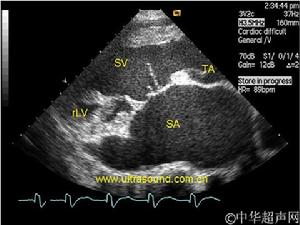

(3) 切面切超聲心動圖檢查:左、右心房之間,房間隔回聲反射消失,四腔切面象上正常情況下,由房間隔、室間隔、二尖瓣、三尖瓣形成的十字形回聲反射改變為T字形回聲反射。